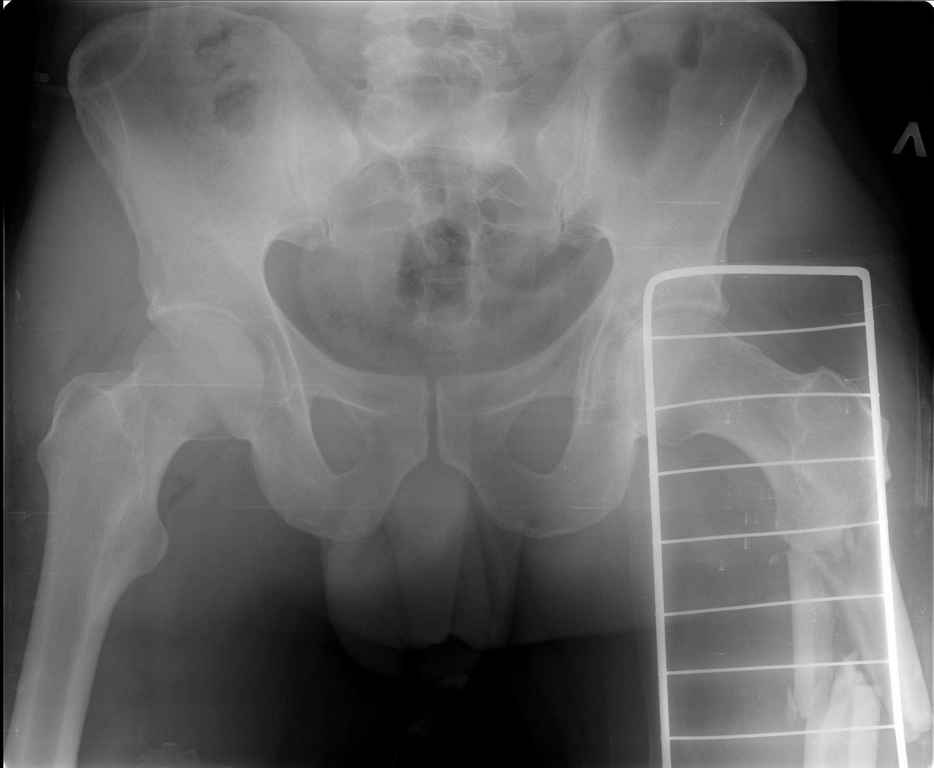

Ds: ТСТ. ЗЧМТ. СГМ. ЗТГК. О/фрагментарный перелом левого бедра. З/оскольчатый перелом с\3 левого плеча. Перелом левого локтевого отростка. З/перелом наружного мыщелка б/берцовой кости в/3 м/берцовой кости левой голени. при поступлении, ПХО раны левого бедра( рана 1х1см по наружной поверхности бедра в с/3) налажено скелетное вытяжение , и гипсовая лонгета на левую в/конечность. Находился в реанимации. 17.02.11 был прооперирован: БИОС левого плеча, о/синтез левого локтевого отростка по Веберу, БИОС левого бедра (длинная версия Fi-Can Sanatmetal диаметр 10мм), мыщелок голени трогать не стали.при остеосинтезе бедра возникли трудности при закрытй репозиции перелома в н/3, в связи с чем решили открыться внизу , отрепонировали без особого труда и выполнили блокирование во фронтальной плоскости 3-мя винтами + 1 винт спереди гвоздя (промазал). Убрал костодержатель, все нормально, контроль ЭОПом стояние отломков нормальное, зашились. На контрольной R-мме на утро выявлено вторичное смещение дистального отломка. Левая нога по сравнению со здоровой удлиннена до 2,5см( это за счет вальгусной установки гвоздя в проксимальном отделе, боялся свалиться на варус). Теперь думаем как поправить положение отломков в н/3, и зафиксировать так чтобы не съехало. Наше предложение расшиться в н/3 бедра, разблокироваться, перелом отрепонировать вновь и установить 1или 2отклоняющих винта в сагитальной плоскости, затем заблокироваться во фронтальной плоскости снова. Помогите советом, как выйти достойно из сложившейся ситуации. Заранее спасибо.

С моей точки зрения удлинение (если таковое имеется) произошло не за счёт вальгусной установки стержня. На контрольной рентгенограмме блокирующие винты точно расположены в шейке бедренной кости и в центре ротации головки. И даже если выбран стержень с максимальным из выпускаемых углом в 135 градусов, он не обеспечит столь значительного удлинения конечности. Увеличенный шеечно-диафизарный угол на контрольной рентгенограмме со стержнем объясняется наружной ротацией конечности при рентгенографии и возникающем при этом проекционном искажении ШДУ. Скорее всего, удлинение конечности объясняется наличием диастаза между отломками в вертельной области.